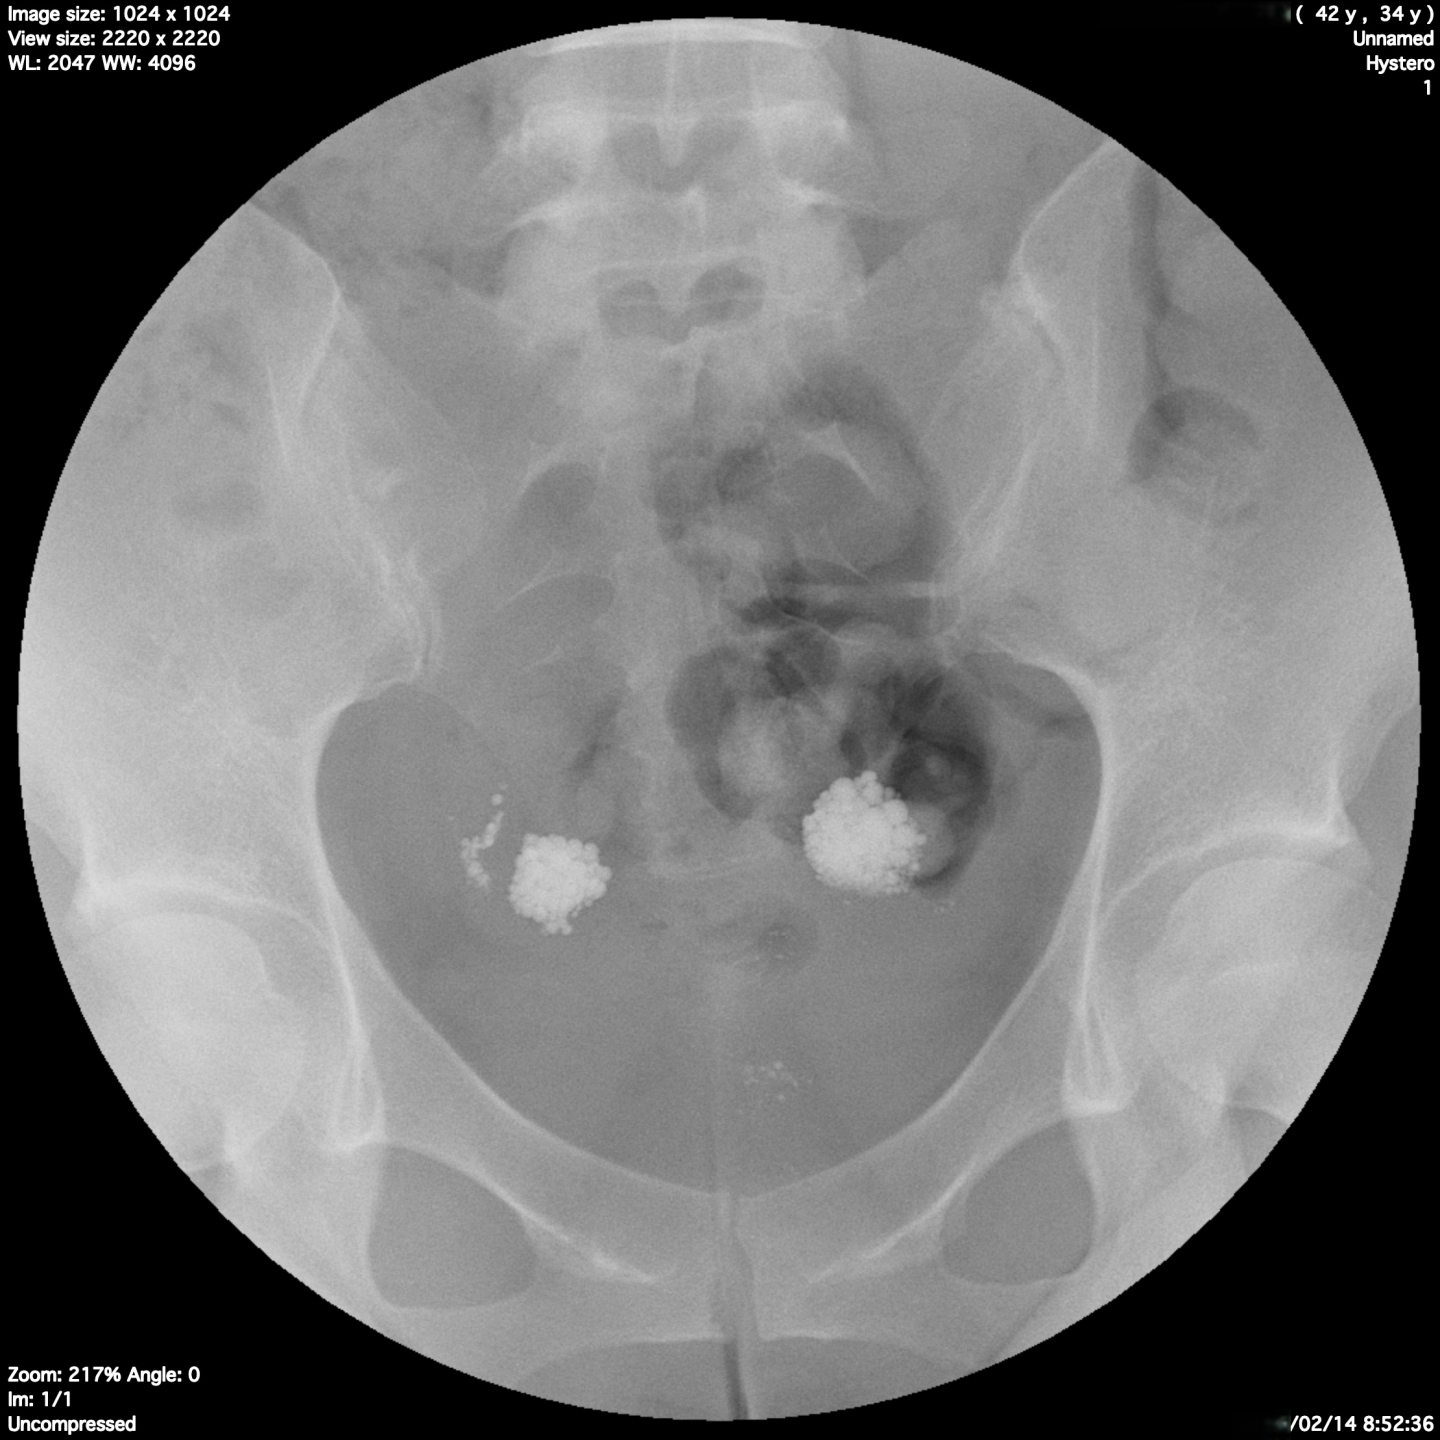

翌日の残像撮影では

両側の卵管采における貯留所見は移動せずそのまま残留している所見を認め、卵管留水症の診断になりました。この場合おそらくは通水検査や超音波造影剤による検査では診断ができなかったと思われます。

これではタイミング療法や人工授精では妊娠はほぼ不可能であり、体外受精もしくは手術的な対応が必要となります。

はじめの段階で卵管造影をしていればもっと早い段階から体外受精となれた可能性があります。

卵管留水症は内容液が子宮内に悪影響を及ぼすため、体外受精の移植においても妊娠率を下げてしまいます。卵管内液体貯留が認められた場合は移植時に穿刺吸引を要したり、腹腔鏡手術により卵管采形成術をしたしますが、再発も認めることがも多く、多くは卵管摘出を必要としたりします。